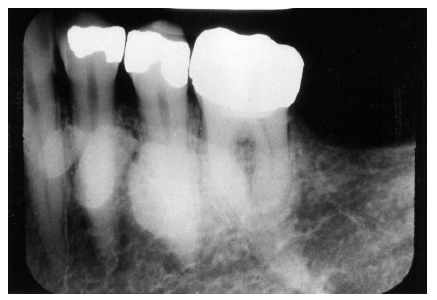

Figure 36 - Pyramidal in #18; Taurodontism in #19

Figure 36

Taurodontism and Pyramidal Teeth

Taurodontism is a fairly common developmental defect in which the affected multi-rooted teeth display apically displaced furcation, producing a pattern of large pulp chambers and short roots. Clinically, the teeth appear normal, but on a radiographic image, they demonstrate a distinct rectangular outline, such as seen in tooth #19 in Figure 36

Taurodontism may affect multiple teeth, but it is limited almost entirely to the molars. It is associated with Kleinfelter’s Syndrome, a syndrome of gonadal defects, appearing in males with an extra X chromosome, which should be suspected whenever taurodontism is encountered in patients with unexplained mental retardation, a tall, thin appearance, long legs and arms, and a distinctly prognathic jaw.

Pyramidal teeth are morphologically similar to taurodontism. They exhibit enlarged, elongated pulp chambers but only single roots, as illustrated in tooth #18 in Figure 36. In effect, the condition appears to represent extreme apical displacement of the furcation, resulting in a single broad root, which, in actuality, is the body of the tooth. The clinician will sometimes encounter both taurodontism and pyramidal teeth in the same patient.